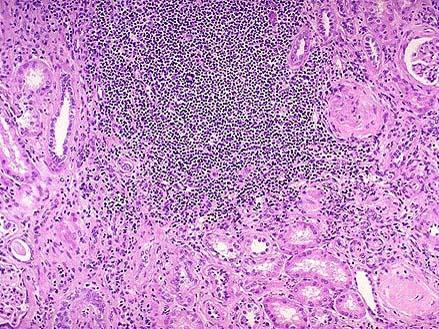

问题 患者女性,53岁,双肾缩小,表面可见不规则瘢痕,两侧改变不对称,切开,皮髓质界限不清,肾乳头萎缩,肾盏和肾盂因瘢痕收缩而变形,肾盂黏膜粗糙;巨检如图,镜下如图所示,应首先考虑的是 ( )

选项 A.高血压性肾病 B.慢性肾盂肾炎 C.急性肾小球肾炎 D.肾结核 E.慢性肾小球肾炎

答案 B